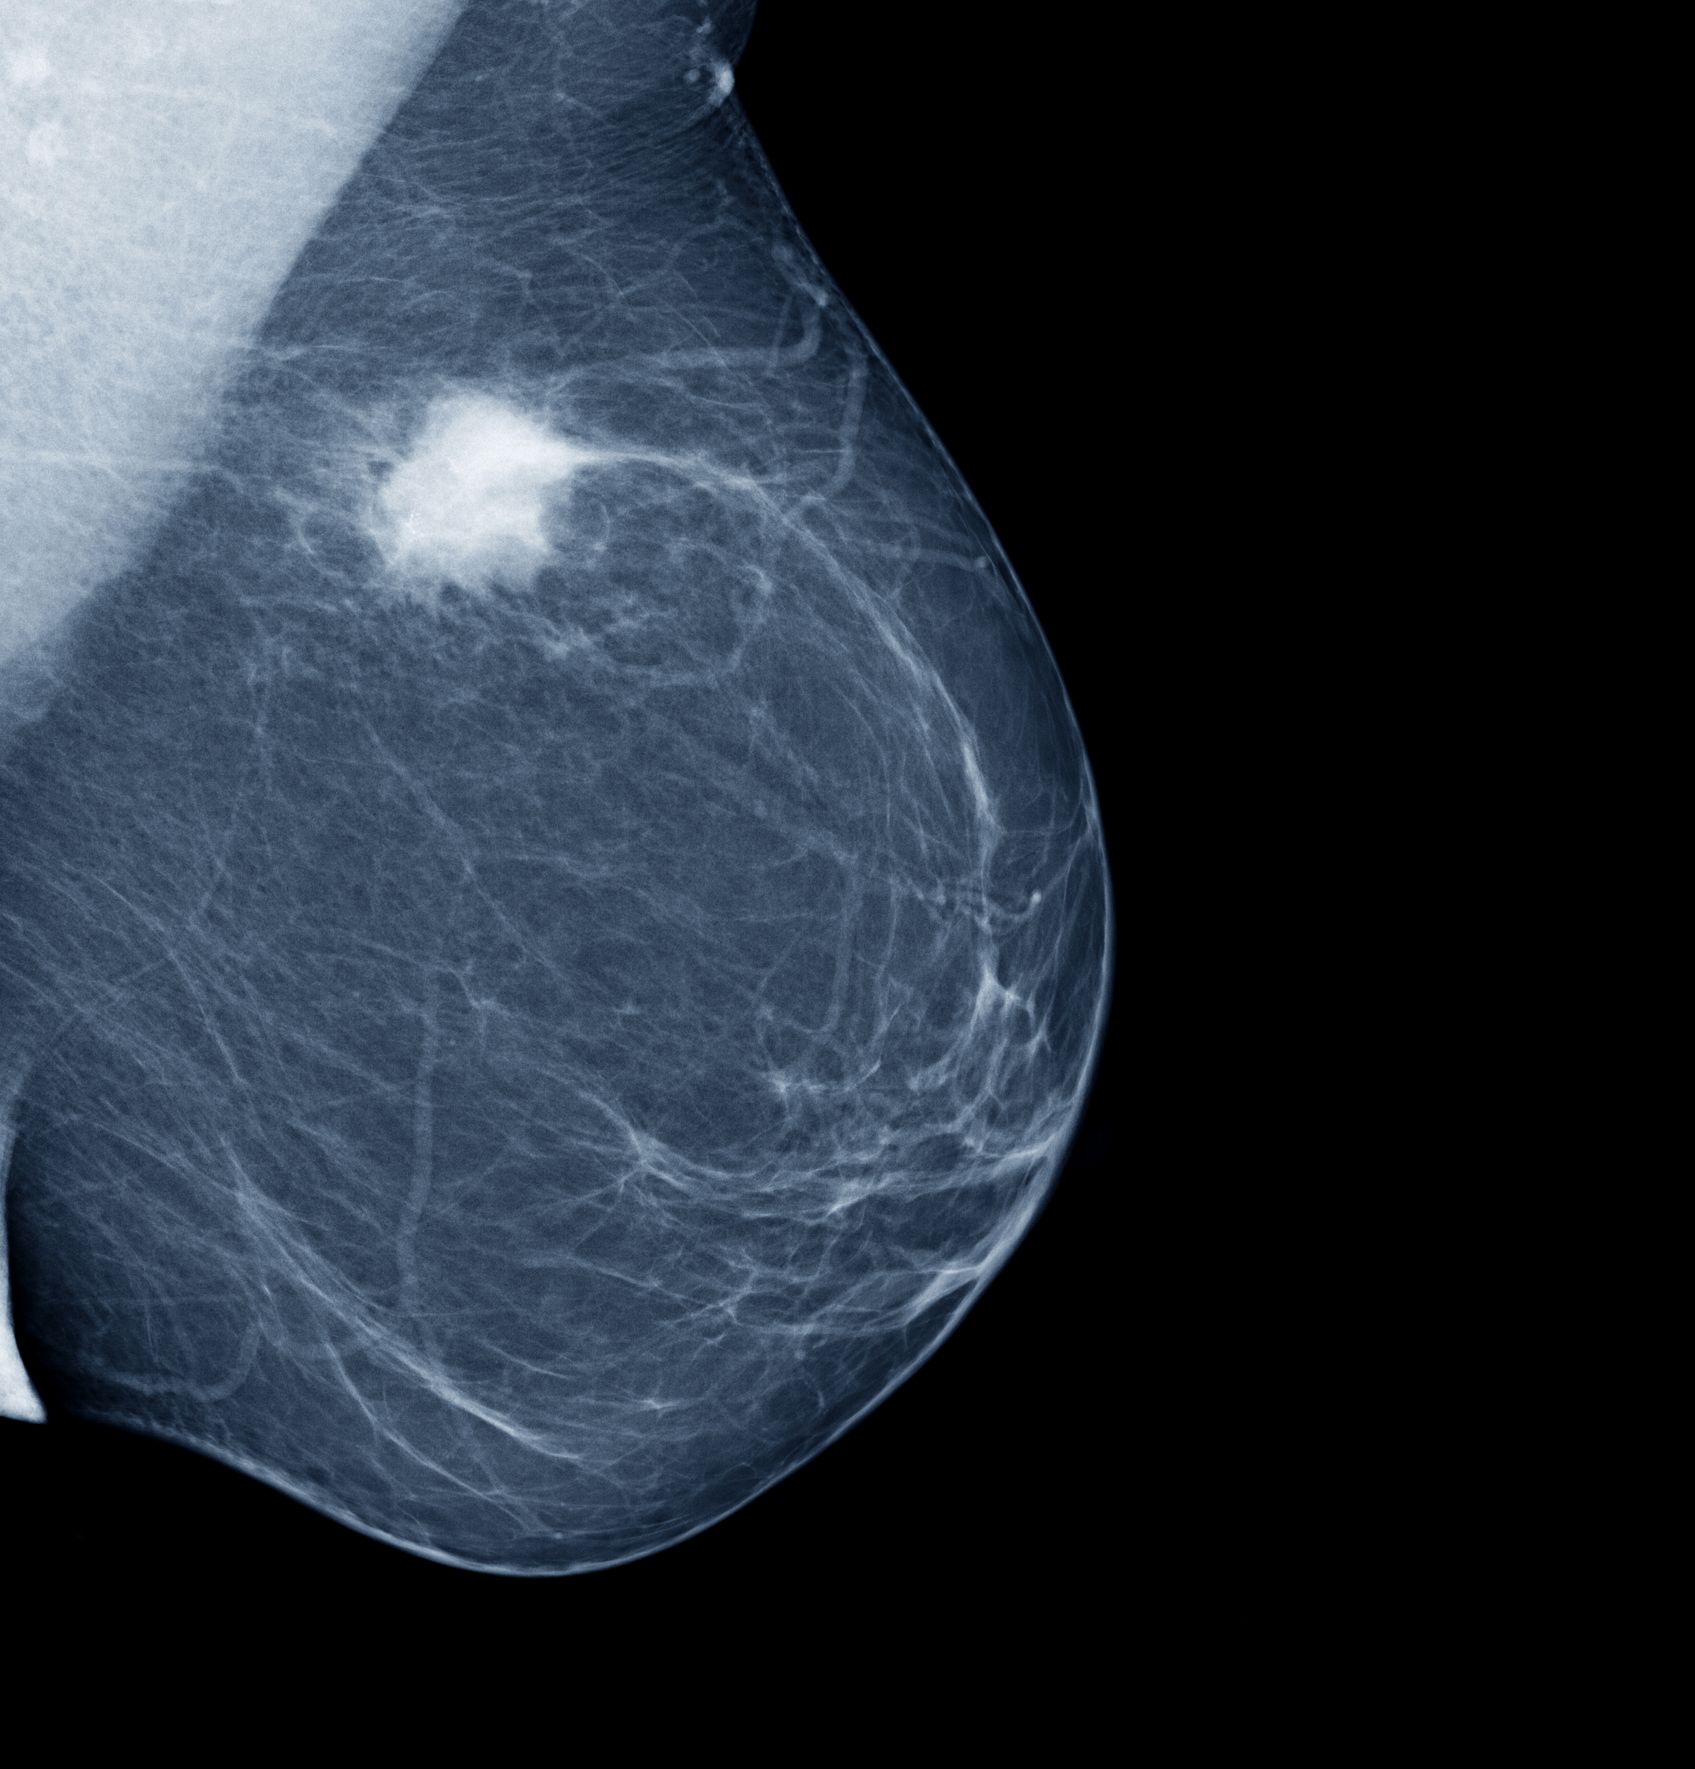

Some warning signs of breast cancer are—. Depending on the specific parts of the body affected, the. These are the signs that led nine women to a doctor, and ultimately a breast cancer diagnosis. Learn more about breast cancer, its signs & symptoms, causes, diagnosis & treatment options. What is stage 0 breast cancer? But just because you develop a lump but in some cases, there are signs that something is going on with your breasts. But at the time of instead, its early signs are discovered on an imaging test. If that's not an option, call your health department, a clinic or a nearby hospital. Is that a lump i can feel? Perhaps the most common sign of breast cancer is the development of a lump in the breast or under the armpit. Cells in the body normally divide (reproduce) only when new cells are needed. Treatment typically involves some type of surgery and depends upon the staging of the cancer, the tumor type, and the person's health. Breast cancer is the most common cancer among women.

Signs Of Breast Cancer How To Check Your Breasts from keyassets-p2.timeincuk.net Common breast cancer signs and symptoms include breast cancer haven is a registered uk charity governed by an unpaid volunteer board. Stay aware and visit your doctor if you develop any of the following five. Learn about the warning signs of breast cancer, including changes in the breast and nipple. But at the time of instead, its early signs are discovered on an imaging test. Every woman's body has a unique ebb and flow, and getting in tune with your own personal rhythm is invaluable for recognizing the signs that you have cancer. Die of breast cancer each year. When the tumor is small in the early stages of breast cancer, it's rarely noticeable to the touch. In this article, we discuss some of the potential signs and symptoms of breast cancer that may occur without a noticeable lump in the breast.

Signs Of Breast Cancer Explained Using Lemons Bbc News from c.files.bbci.co.uk How common is breast cancer? It just means that more tests are needed to find out what's going. Most breast cancers are diagnosed when a tumour has grown from within a duct or lobule into the surrounding breast tissue. Breast cancer signs and symptoms. Learn about the warning signs of breast cancer, including changes in the breast and nipple. Some warning signs of breast cancer are—. Cells in the body normally divide (reproduce) only when new cells are needed. Signs in menmen and breast cancer.

What's new in breast cancer research? Keep in mind that these symptoms can happen with other conditions that are not cancer. Stay aware and visit your doctor if you develop any of the following five. Anyone who notices any of these changes should see a doctor. In particular, if they were aged under 50 when. New lump in the breast or underarm (armpit). Is a lump on breast cancerous? Most people who have breast cancer symptoms and signs will initially notice only one or two your doctor can check for breast cancer before you have any noticeable symptoms. If you have insurance, your insurance company may also have a list of providers in your area. Most breast lumps are not cancerous, but it's. Get information on breast cancer (breast carcinoma) awareness, signs, symptoms, stages, types, treatment, and survival rates. Read about different tests, prevention and early signs. When the tumor is small in the early stages of breast cancer, it's rarely noticeable to the touch.